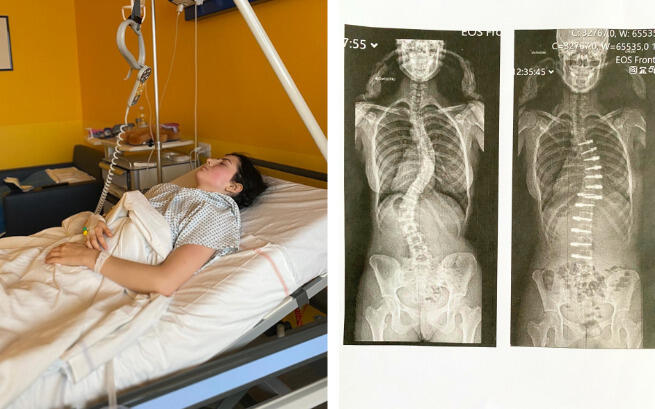

Zobacz Martę po operacji! I walcz z nią do końca!

15 listopada w Mediolanie odbyła się operacja kręgosłupa, która była dla naszej Martusi jedyną szansą na powrót do życia bez bólu i ograniczeń. Udało się zebrać prawie 70% potrzebnej kwoty, co pozwoliło nam podjąć ten najważniejszy krok!

Operacja, przeprowadzona przez niezwykle utalentowanego profesora Berjano i jego zespół, zakończyła się sukcesem. To była skomplikowana procedura, ale dzięki doświadczeniu lekarzy przebiegła pomyślnie. Marta dostała od Was i od nich nowe życie – życie, w którym powoli, krok po kroku, odzyskuje siły i nadzieję.

Marta od zawsze była ambitna. Najlepszym świadectwem tych słów jest mnogość jej zainteresowań. Trenuje gimnastykę sportową, śpiewa, tańczy, pływa. Stara się czerpać z życia jak najwięcej. Nie jest to jednak łatwe. Nasza córka zmaga się ze skoliozą trzeciego stopnia. Choroba szybko postępuje, próbując odebrać jej wszystko, co kocha.

Niestety, mimo jej determinacji, skolioza się pogłębiła. Jej dalszy rozwój może spowodować ucisk kręgosłupa na organy. Obecnie noszenie gorsetu powoduje poważne skutki uboczne, jakimi są problemy z oddychaniem i trawieniem. Kiedy Martę atakuje ból, jest zdana tylko na siebie. Bardzo trudno widzieć nam ją w tym stanie. Jedynym ratunkiem jest jak najszybsza operacja.

Wszyscy polscy specjaliści, do jakich się zgłosiliśmy, proponują Marcie usztywnienie całego kręgosłupa. W kraju nie ma innej metody leczenia tak postępującej skoliozy. Nie możemy się na to zgodzić. Zabieg odebrałby córce mobilność. Sprawiłby, że nasze dziecko musiałoby na zawsze pożegnać się ze sprawnością fizyczną, bezpowrotnie porzucając swoje pasje.

Po latach intensywnych poszukiwań udało nam się znaleźć rozwiązanie. Trafiliśmy do jednej z mediolańskich klinik, gdzie Marta ma szansę na operację metodą, która nie usztywni jej kręgosłupa. Niestety, po fali radości przyszło uczucie smutku i niepewności. Koszt zabiegu jest ogromny.